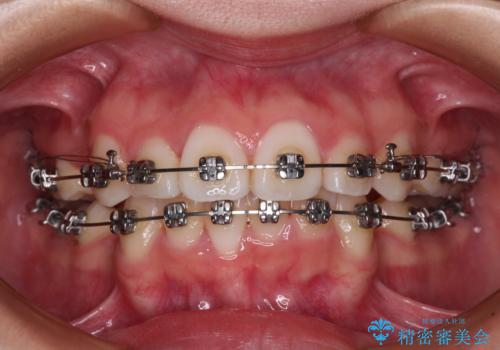

- メタルブラケット

上下左右第一小臼歯4本を抜歯し、ワイヤー装置にて歯列を整え、さらには少しでも口元を引っ込めるよう矯正治療を行うこととしました。

上下の骨格での左右差が小さかったことと、抜歯矯正であったことで、上下正中の位置をきれいに合わせることができました。